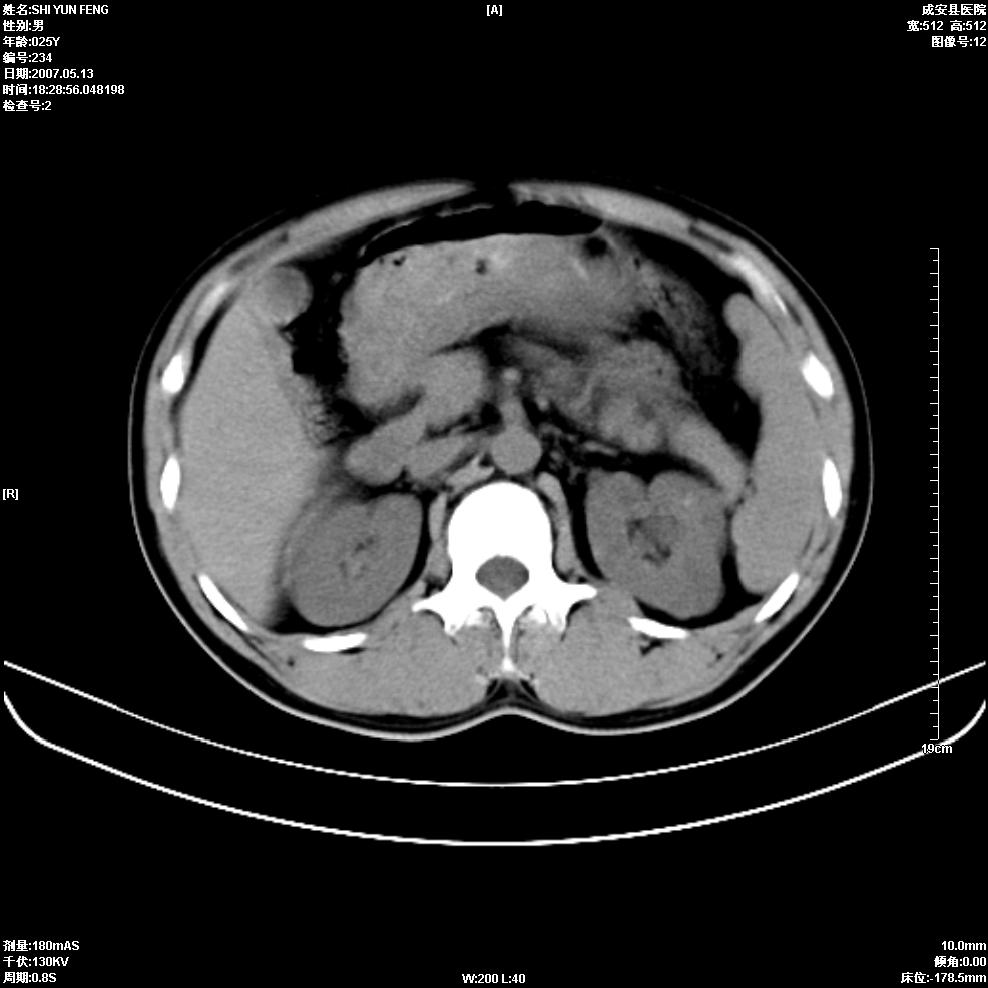

以下是引用zhangzhongshou在2007-5-16 7:36:00的发言:[br]多发性肾囊肿,左肾多发结石。不是多囊肾,楼主箭头所指多考虑左肾囊肿内结石或钙乳,髓质海绵肾不完全除外。[br][br][本贴已被 zhangzhongshou 于 2007-5-16 7:37:18 修改过][br][br][本贴已被 zhangzhongshou 于 2007-5-16 18:15:09 修改过]